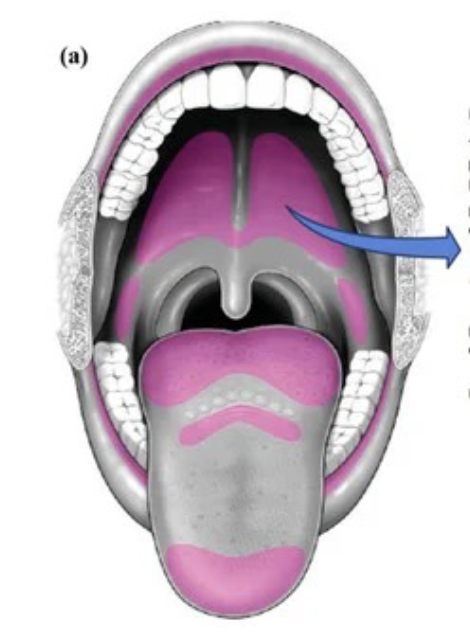

舌頭

Structure

- Terminal sulcus(terminalis)分前後

Nerve

運動

感覺

- 根部 taste/ general sense

- 後 taste/ general sense

- 前

- Taste: Chorda tympanic

- General sense: Lingual n